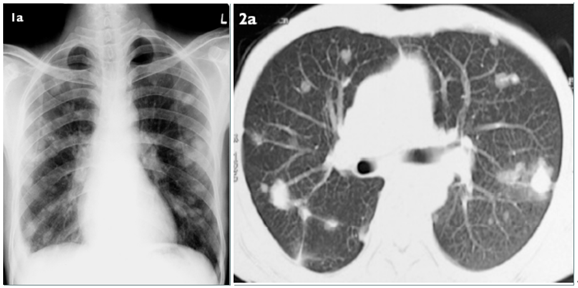

影像学特点

单发或多发的肺实变,常伴空洞。

底部贴近胸膜的楔形阴影。

单发或多发的小结节和晕征。

反晕征。

气管内病变。

其他:胸腔积液,累及纵隔、肋骨等。

图片

注:免疫缺陷的患者,左肺舌叶肺坏死,新月形空洞形成

注:底部贴近胸膜的楔形阴影

注:单发或多发的小结节和晕征